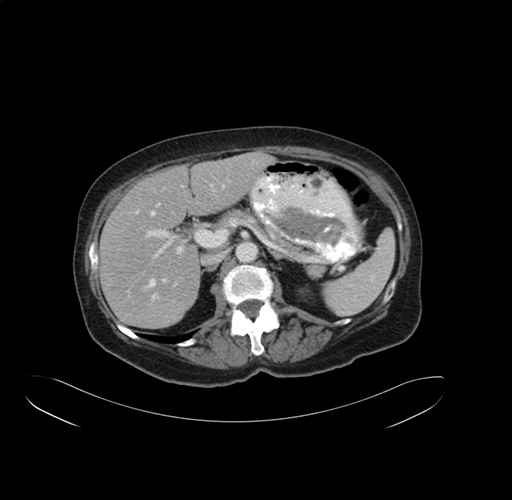

Pre-Chemo: Axial Venous

Axial Venous